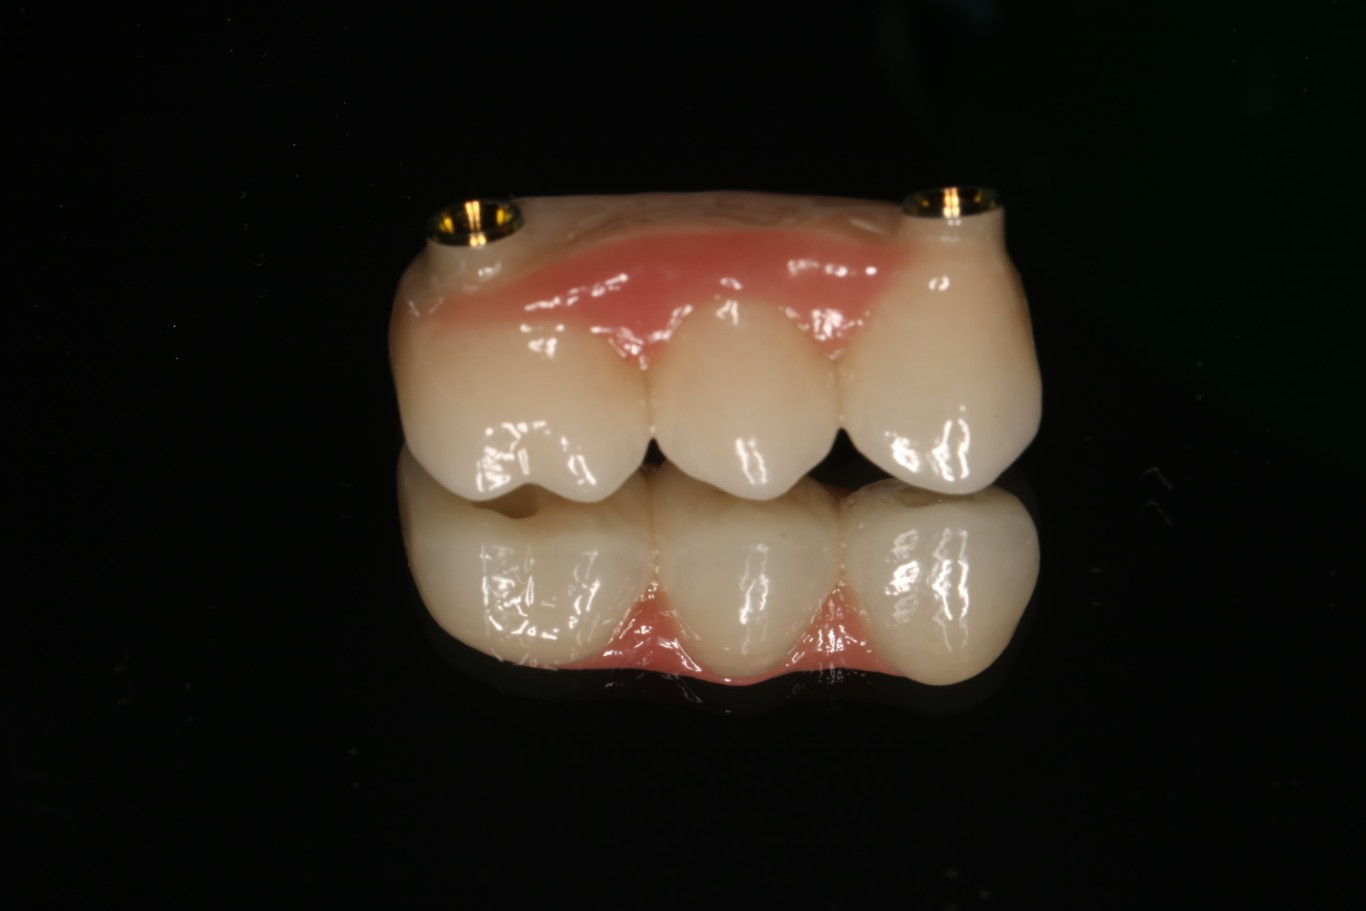

3. Protezy na koronach teleskopowych – elegancja i precyzja

Korony teleskopowe to najbardziej zaawansowane technicznie rozwiązanie w protetyce ruchomej na implantach. System działa na zasadzie “korona w koronie” – na implanty osadzone są stałe korony (korony pierwotne), a na nie nakładana jest proteza z koronami wtórnymi, które idealnie do nich przylegają.

Zasada działania:

Na każdy implant zakręcana jest precyzyjnie wykonana korona pierwotna. Proteza posiada wewnątrz odpowiadające im korony wtórne. Połączenie typu teleskopowego zapewnia doskonałe dopasowanie i retencję mechaniczną – proteza “wsuwana” jest pionowym ruchem i trzyma się niezwykle stabilnie bez dodatkowych zapięć.

Zalety koron teleskopowych:

– Najwyższa estetyka – brak widocznych haczyków, klamr czy zapięć. Proteza wygląda jak naturalne zęby

– Precyzyjne dopasowanie – system teleskopowy zapewnia idealne przyleganie i równomierne rozłożenie sił żucia

– Łatwość serwisowania – konstrukcja pozwala na naprawy i modyfikacje

– Higiena na najwyższym poziomie –

możliwość wyjęcia protezy i dokładnego oczyszczenia wszystkich elementów

– Możliwość rozbudowy – w przypadku utraty kolejnych zębów można dodać elementy do istniejącej konstrukcji

– Niezawodność – retencja mechaniczna sprawia, że system jest bardzo odporny na zużycie